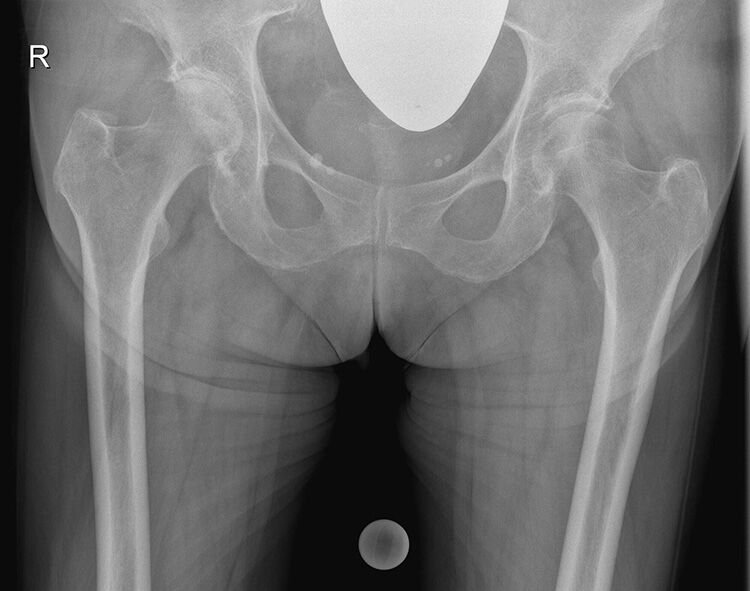

Αρθροπλαστική ισχίου με τσιμέντο στην κοτύλη

Ανδρας 67 ετων συνταξιούχος με προστατεκτομή και ακτινοθεραπεία πριν 4 χρόνιαπροσήλθεμε εντονο πόνο και δυσκαμψία του δεξιού ισχίου! Ο ακτινολογικος έλεγχος εδειξεοστεοαρθρίτιδα. Εξαιτίας του πόνου αποφασίστηκε να γίνει αρθροπλαστική ισχίου. Λογω